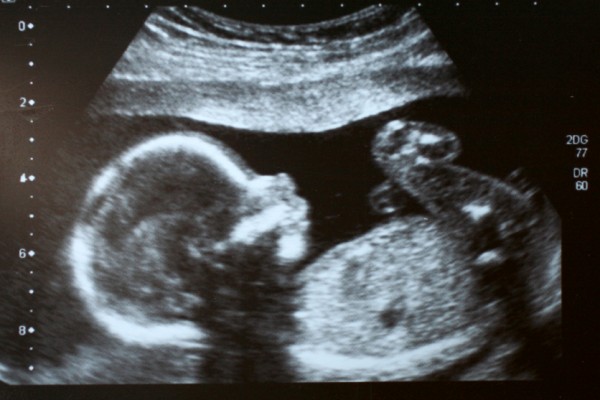

- 3D/4D ultrazvučni pregled ploda, tzv. anatomy scan